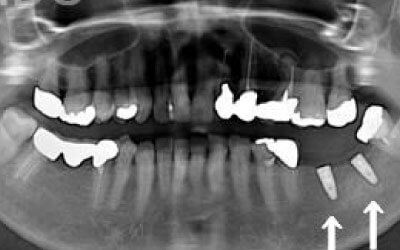

CTでは骨や歯の状態などを3次元で見ることができ、正確な距離を測ることも可能です。

骨の厚みや傾き、神経の位置などを事前にしっかり計測することで安全なインプラントが可能となります。

骨が薄い場合は、そのままインプラントすることはお勧めできません。

ただ、事前に骨を増やす治療をしたり、インプラントと同時に骨を増やす治療をしたりすればインプラントをすることは可能です。

2 神経を傷つけるリスク

顎の骨の中を通っている神経を傷つけるリスクがあります。

ただ、事前にしっかりCT撮影して三次元的に神経までの距離を計測して治療計画を立てれば心配することはありません。

今回のご質問ですが、抜けた部分の骨が薄いなどの理由で「インプラントはできない」と言われた可能性があります。

前歯はもともと骨が薄く、歯が抜けると時間の経過とともにさらに骨が痩せてきてしまうので、インプラント治療の難易度が高い場所です。

ただ結論からお話すると、インプラント治療は可能です。

なぜなら、もし仮に骨が薄くても、骨の治療によって厚みが増せば、安全にインプラント治療が行えるからです。

1)インプラント治療を行う前に、骨の治療が必要かもしれません。

4)骨の状況をしっかり把握するためにも、CT撮影が必須となります。